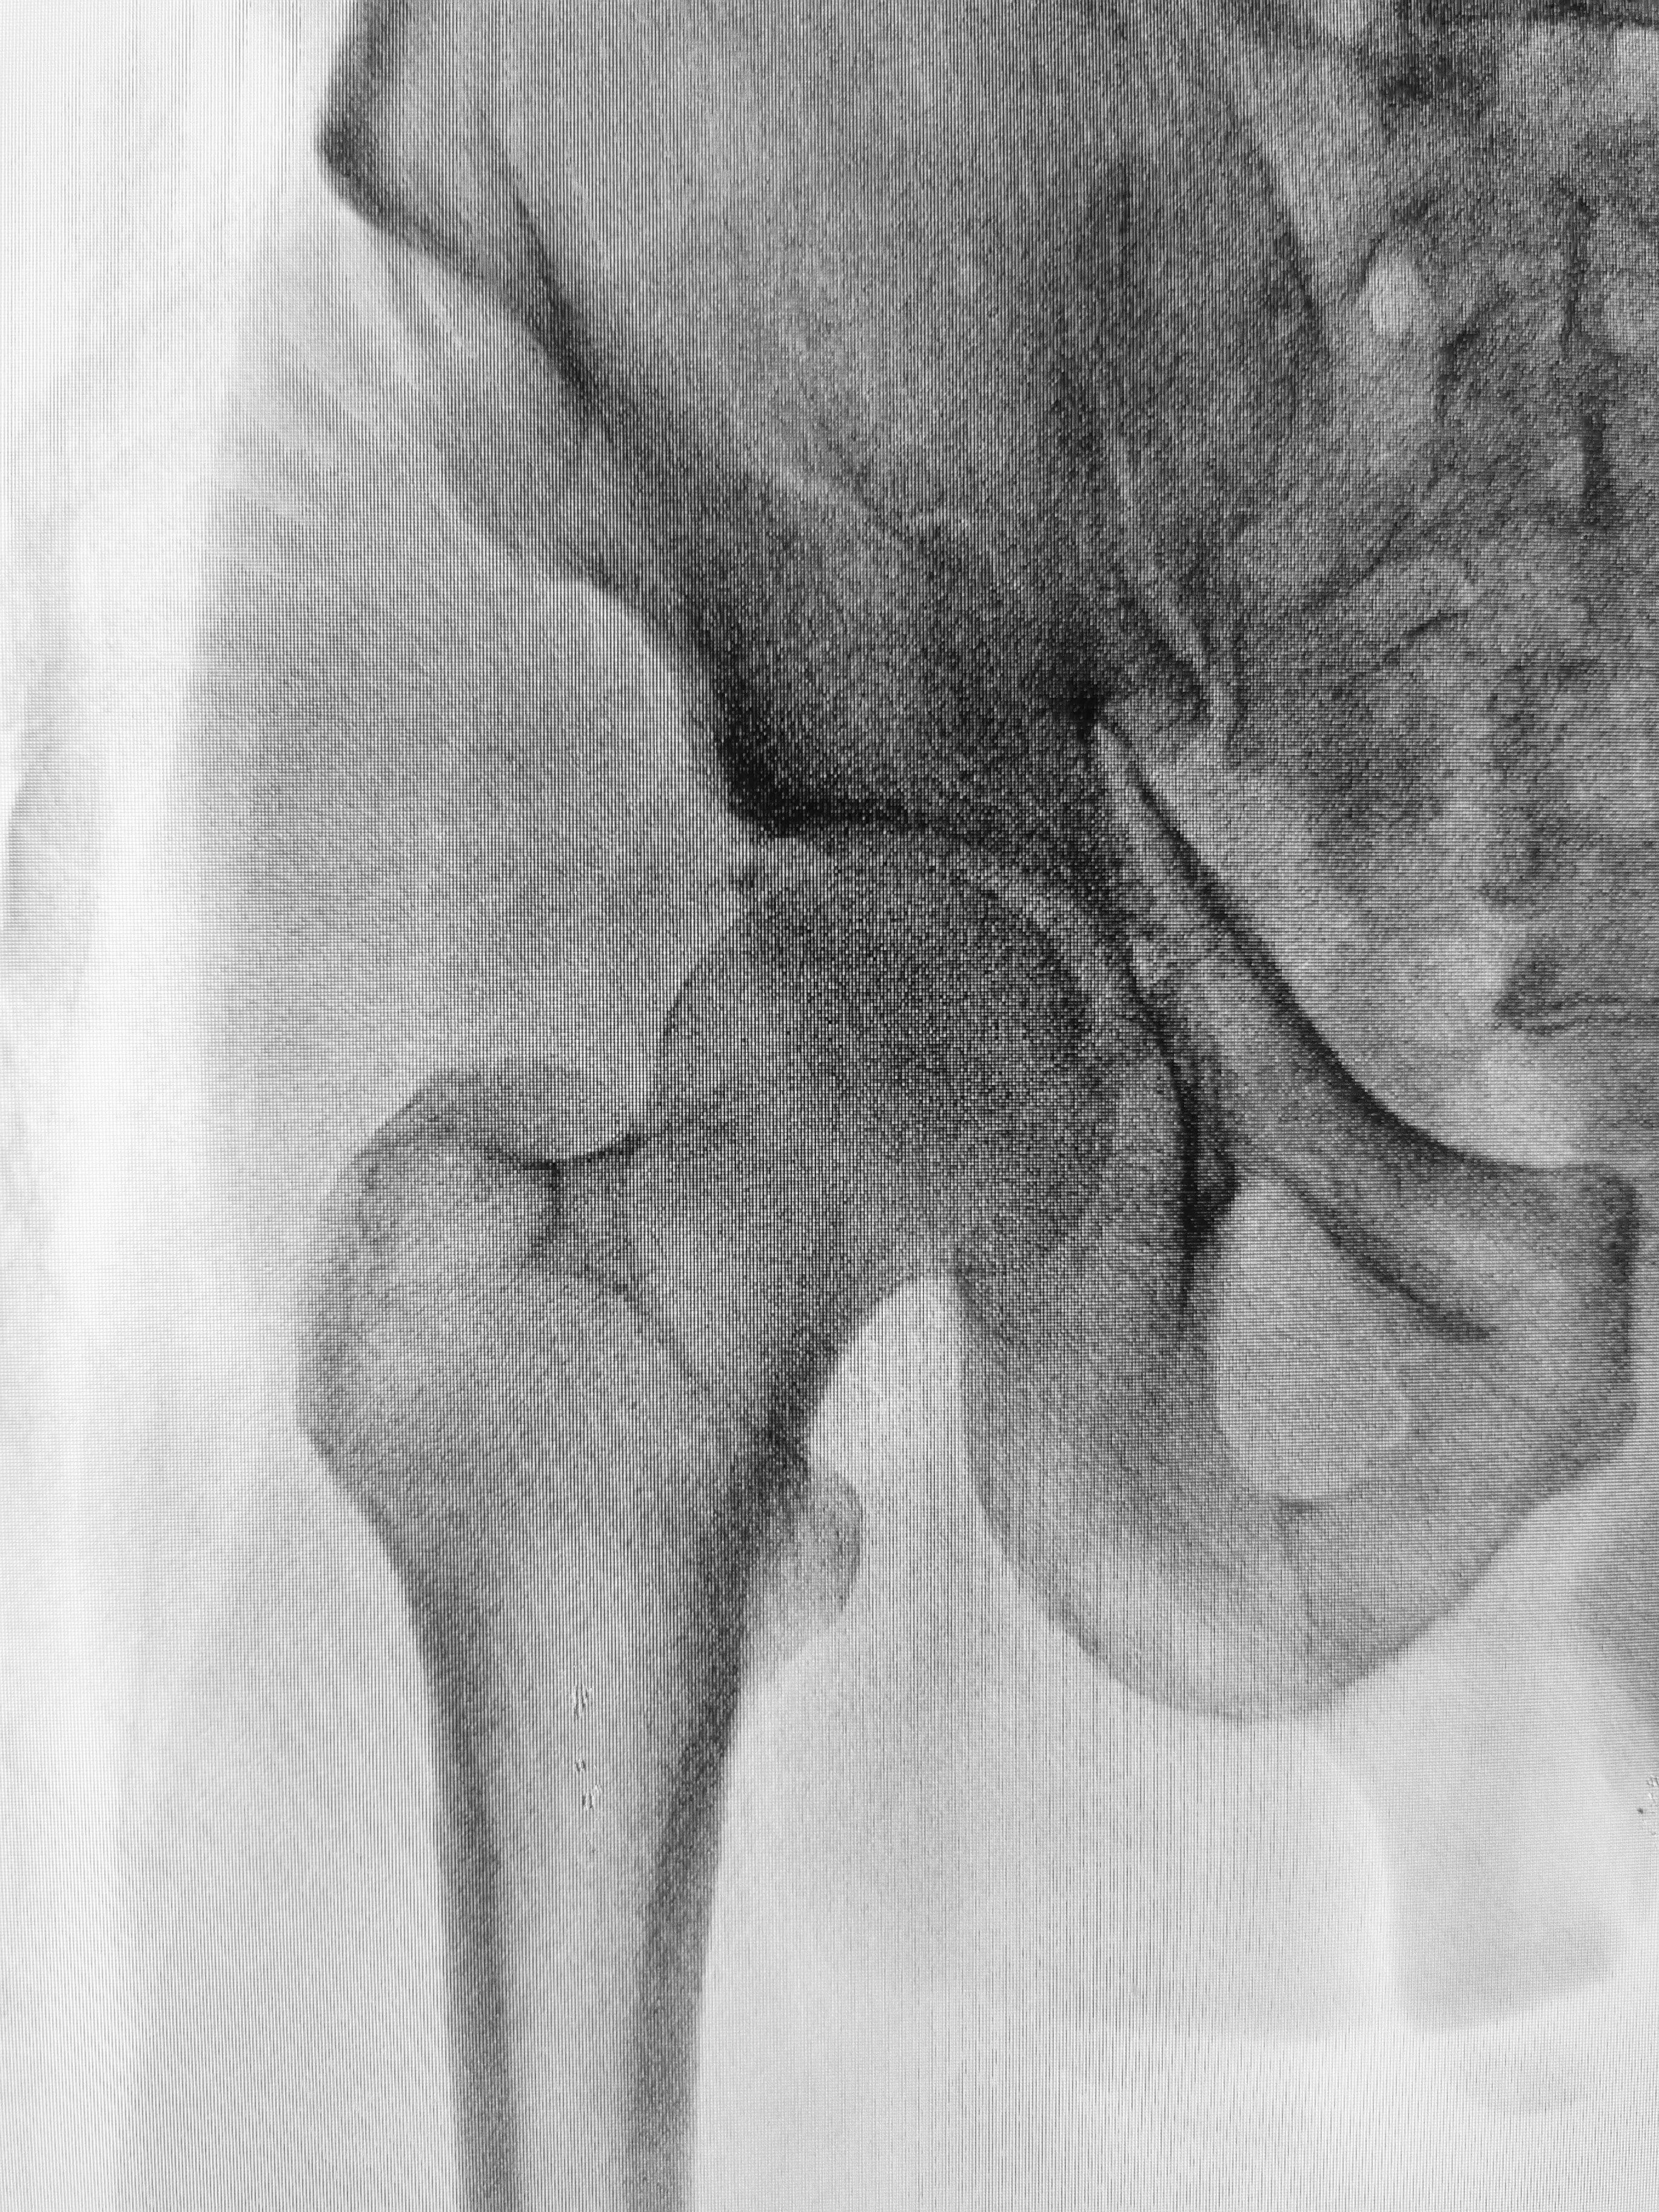

His pelvis, like yours, was comprised of several bones, the ilium, ischium, pubis, sacrum and coccyx and jointly they unite spine and legs. The head of the femur, or thigh bone, plugs into the pelvis at the acetabulum, as a ball-and socket joint, and it was at this union the great man was able to initiate his famous rotations.

Hip fractures usually occur at the neck where the femur angles to the head, as this area has an inherently poor blood supply. Surgery is required to replace either the top of the femur alone or maybe in conjunction with the “cup” it sits in with metal, plastic or ceramic components.

Come what may, the most common reason for hip pain and disability is osteoarthritis due to wear and tear, a function of age and obesity. About 58 million Americans have osteoarthritis and in roughly half, their activities are limited by disease. This diagnosis is always on my mind when I see an older person with hip pain, although the source may be in the spine, being referred to the hip, and likewise, hip pain can be referred to the knee. Once diagnosed by clinical examination and radiographs, treatment will initially address pain, exercises to strengthen muscles, occupational therapy to teach new ways to deal with activities of daily living and hip replacement, when the patient asks themselves “am I ready” to have this operation. A hundred years from now – and hopefully much sooner – we will have regenerative medicine technologies with stem cells, drugs and tissue scaffolds to repair diseased or traumatized joints.